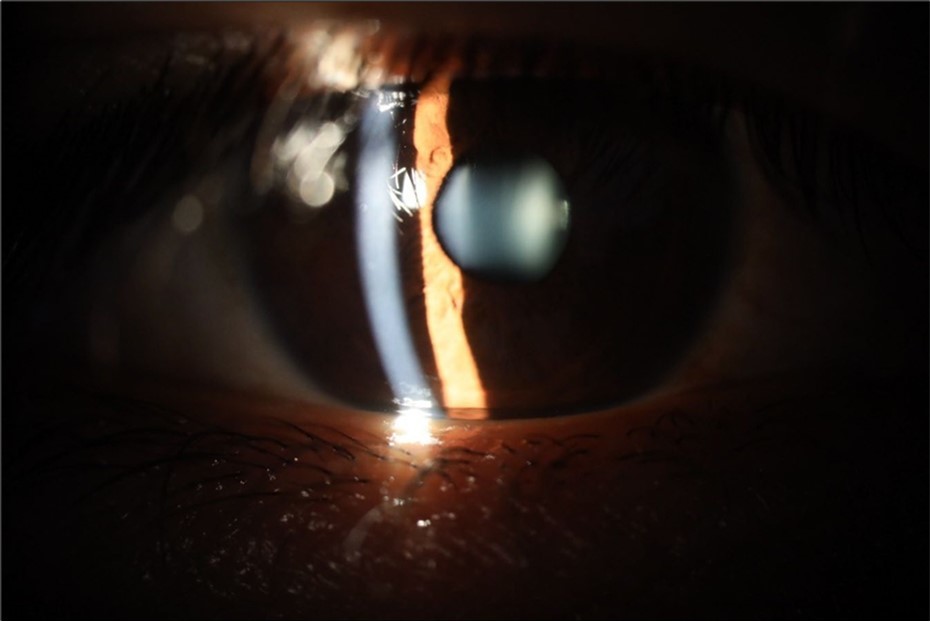

Figure 5.The slit-lamp photograph shows the anterior segment, relatively unscathed, in terms of transparent media (Cornea, crystalline and vitreous).

Figure 15.The photograph shows better specular reflection, compared to the first day of the exam.

Figure 16.The anterior segment of the right eye shows the vitreous with greater transparency. The cornea and lens, as well as the anterior chamber, are in good condition.

Figure 25.Mirror reflection of the affected eye (right side), with good appearance. This indicates that the transparent media of the eyeball (Cornea, anterior chamber, lens, and vitreous) are in good condition.

Figure 26.The macrograph of the anterior segment of the right eye (affected) shows very good transparency of the cornea, anterior chamber, lens, and vitreous.

Figure 31.The photograph of the right eye shows an almost normal mirror reflection, as well as a better pupillary dilation.

Figure 32.The macro photograph of the right eye shows us a cornea, anterior camera, and crystalline lens in very good condition.